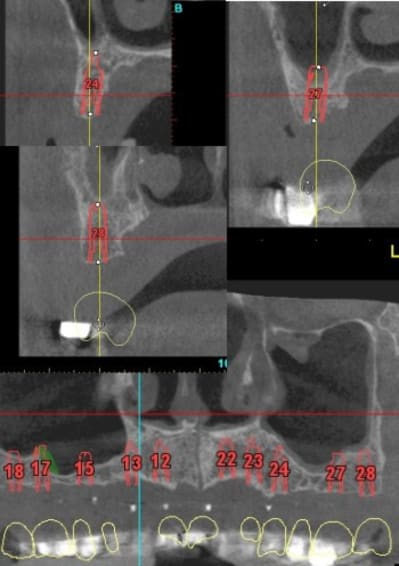

vis de cicatrisation sur une expansion réalisée en mars 09 à Sallanches implants en 13/14/15/18 pour une barre et PT.

Interessante car fracture de l'os vestibulaire y compris de la bosse canine, vitalos mais pas de vis d'ostéosynthese, et comme je sais que le doute est toujours present, ouverture large, avec décollement plus que necessaire pour controle.

sur l'implant en 14 une feuille d'os , en 13 un petit creux en mesio vestibulaire et 15 nickel.

18/17 et 28/ 27 en flapless (4 SL )

le gros point noir c'est 15, je ne suis pas sur que la solution soit de poser un implant de suite.

13 et 12 ça va le faire il te restera 22 23 et 24.

merci Thomas je suis bien rentré (croisé 6 paires de "jumelle" avec des habits bleus, mais à chaque fois coup de bol...)et je ne résiste pas au plaisir de passer le pano de notre ami.

Bien sur c'est du travail "d'amateurs", les axes sont nuls mais il semblerait que ton patient va l'avoir son amovo-inamovible!